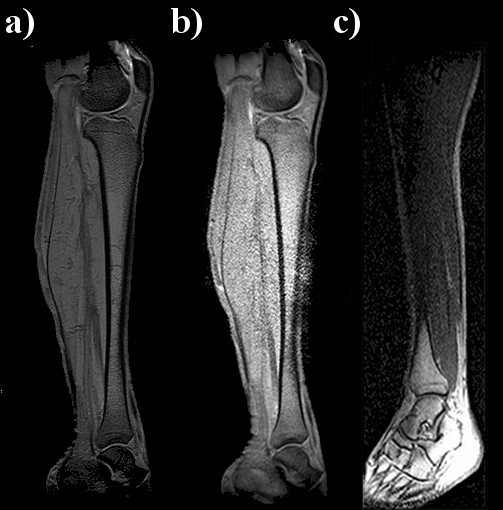

T1-weighted images of a healthy volunteer’s entire leg were obtained using: a) the whole-body coil, b) the PPWG and c) a pair of RF coils are shown in Fig. 9. As shown, good quality images were acquired with this simple waveguide and the two circular-shape flexible coils. The FOV used to cover the entire leg is much larger than the coil size (11 cm diameter), and the B1 field is not attenuated along the entire leg; moreover at the waveguide ends, a signal increase is observed. An extra 5 cm can also be gained with the waveguide scheme. It is also important to highlight that one single FOV covering the entire leg was applied such that digital processing was not necessary as reported in [16]. Additionally, the leg image acquired with the pair of single RF coils (Fig. 9.c) shows really poor quality image. The regions near the two surface coils show very good contrast and a good image quality compared to the central region. Nevertheless, an increment in the noise level is also observed in the waveguide image (Fig. 9.b)) for the central region; this is likely due to the fold over effect caused by a FOV whose size is greater than the common FOV sizes used in clinical practice and, no fold over suppression was applied.

Figure 9. T1-weighted images of a human leg acquired with the whole-body birdcage coil (a) and PPWG + pair of RF coils (b) and the pair of coils only (c). The image acquired with the twMR approach shows an increment of noise at the centre of the leg not present in the other two leg images. The image obtained with the pair of coil shows a really poor signal compared to the other images. An evident signal contrast between the central and the foot regions can be appreciated: the higher image intensity can be explained by the close proximity of the coil to the foot (Fig. 1.c).